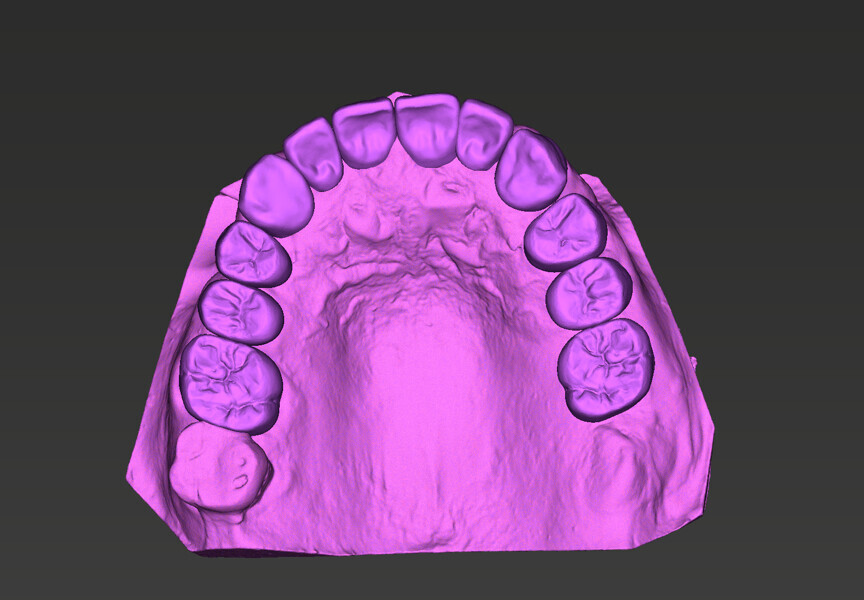

Compromised maxillary dentition treated with Straumann Pro Arch and a digital workflow